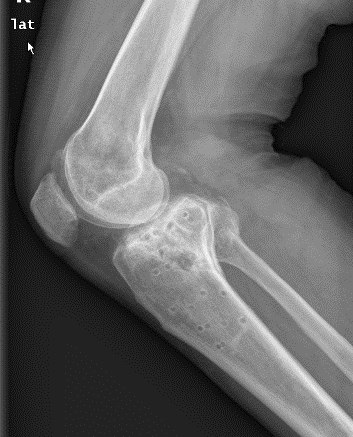

1、图1-2 术前X片见骨折似乎不是特别严重

2、图3-6 术前CT见胫骨平台严重塌陷、劈裂

胫骨平台骨折的病人,如果在30年前大多数医院应该会选择保守治疗。那时CT尚未普及,而仅凭X片会低估其损伤的严重程度,容易产生可不必手术的假象,也难以准确判断骨折移位情况。即使想做手术,也没有什么好的内固定可供选用。